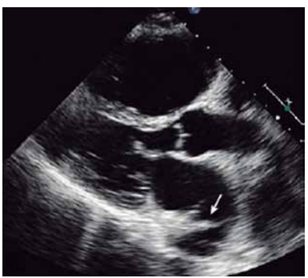

Criança, sexo masculino, 5 anos, realiza ecocardiograma para avaliação de sopro cardíaco.

(Arquivo pessoal; imagem utilizada com autorização)

A imagem indica: